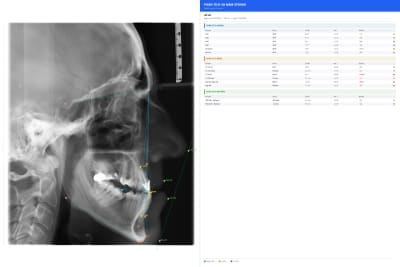

Je suis repartie de zero

La nouvelle version permet de :

- créer un patient

- choisir la langue d'interface ( Vietnamien par défaut )

- zoomer /bouger la radio ( les points déjà placer restant en position )

- ajuster les contrastes/luminosité

- bouger les points déjà mit en place pendant et après l'analyses ( les valeurs étant ajusté en temps réel )

Le logiciel est finie et l'on va tester ça avec plusieurs dentistes.

- plusieurs analyses disponible

- les valeurs normale pour différente population

- possibilité d'avoir et de modifier les tracers

- super imposition

- export des analyses en JPEG et PDF

- Vietnamien/Français/Thai/Espagnol/Anglais

Une fois tester je mettrais un lien pour ceux qui veulent le télécharger.